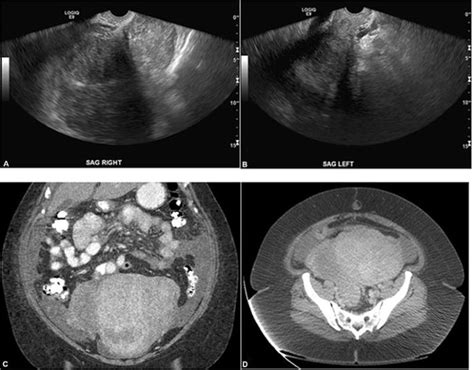

Ovarian cysts or tumors can also impact the visibility of the left ovary on ultrasound. If a cyst or tumor is large enough, it may overshadow the surrounding structures, including the left ovary, making it difficult to identify. In such cases, additional imaging techniques, such as MRI or CT scans, may be recommended to obtain a clearer picture of the ovary and to assess the nature of the cyst or tumor.

If the left ovary is not visible on an ultrasound, further evaluation or follow-up may be required. This could involve repeat imaging with alternative techniques, such as transvaginal ultrasound or MRI, or consultation with a specialist, such as a gynecologist or reproductive endocrinologist. Effective communication between the healthcare provider, radiologist, and patient is crucial to ensure appropriate next steps and address any concerns adequately.